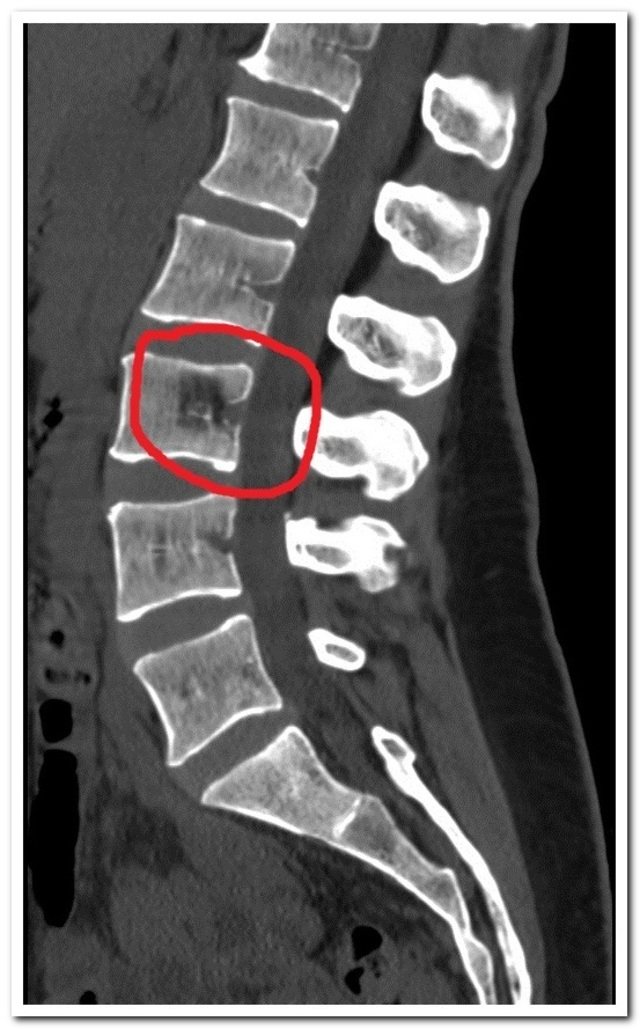

Стандартным диагностическим методом при выявлении гемангиолипом являются рентгеновские снимки, на которых будет видна ячеистая структура, а также уменьшение высоты позвонка, что характерно для данной патологии.

При подозрении на сдавливание опухолью спинного мозга обязательно проводится магнитно-резонансная томография. В ходе обследования выявляется степень повреждения позвонка. При малых размерах опухоли лечение не требуется, но необходимо регулярное наблюдение. Периодический контроль нужен для того, чтобы не пропустить возможный рост новообразования.

Из дополнительных методов наиболее часто применяют рентгенографию. Исследование является распространённым, но при гемангиолипоме оно не обладает достаточным уровнем информативности. В некоторых случаях снимок, на котором гемангиолипома в теле позвонка, проявляется изменением структуры, что предусматривает использование более высокотехнологичных способов.

Магнитно-резонансная или компьютерная томография позволяет выявить опухоль на начальных стадиях развития заболевания. Кроме того, они с точностью определяют уровень поражения и вовлечение других отделов в патологический процесс. Из-за относительно высокой стоимости и отсутствия аппаратов в лечебных учреждениях многие пациенты не выполняют данное сканирование.